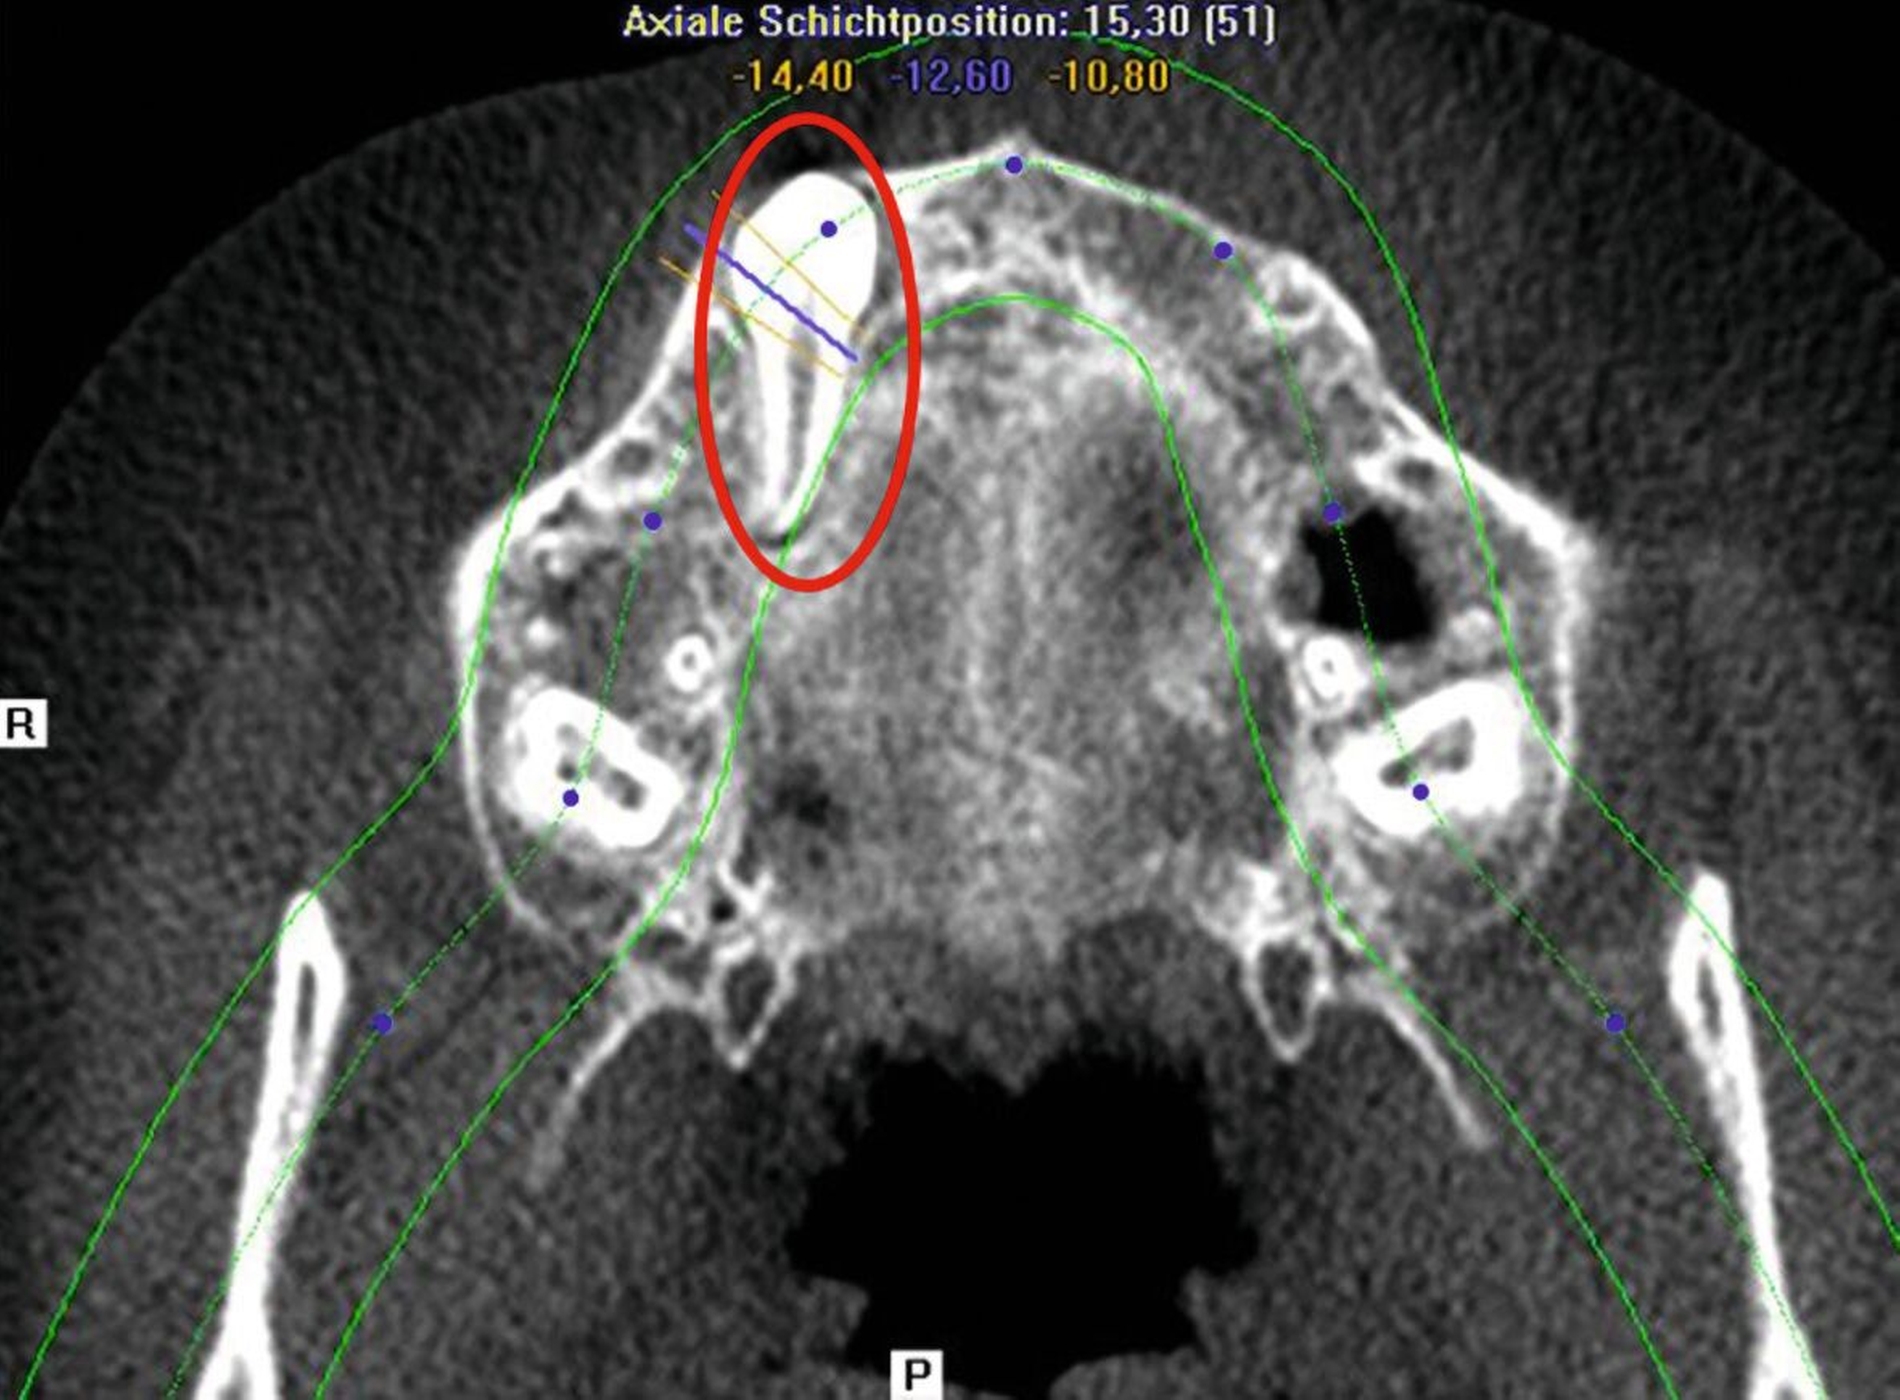

Zwei Jahre nach einem komplexen Zahntrauma mit komplizierter Kronenfraktur 21 und endodontischer Versorgung stellte sich eine elfjährige Patientin mit nun ausgedehnter apikaler Beherdung am Zahn 21 bei uns vor (Abbildung 1). In ihrer Krankengeschichte hatte die Patientin im Alter von vier Jahren eine Leukämie überwunden. Es wurden keine weiteren gesundheitlichen Probleme angegeben. Im OPG zeigt der Zahn 21 eine periapikale Aufhellung im Sinne einer Parodontitis apicalis chronica mit nun akuten klinischen Schmerzen (Abbildung 1).

Zur weiteren Abklärung wurde eine dreidimensionale Aufnahme durchgeführt (DVT). Dabei bestätigte sich die erhebliche Osteolysezone im apikalen Bereich des vormals traumatisierten Zahnes 21. Der Zahn 13 stellt sich hoch verlagert am Nasenboden dar, während es bei dem persistierenden Milchzahn 53 zu einem natürlichen Lückenschluss in regio 13 gekommen ist (Abbildung 2).